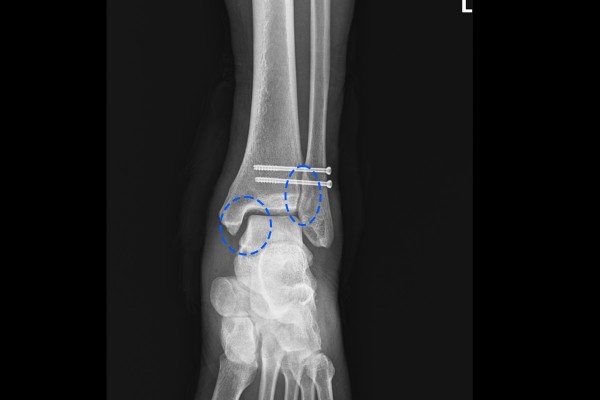

반면, 통증이 있는 왼쪽 발목은 내측 공간이 벌어져있는데, 이는 삼각인대가 파열됨을 의심할 수 있습니다. 또한 경골과 비골이 겹치는 공간도 우측 발목에 비해서 작아진 것이 확인됩니다. 경골과 비골이 겹치는 부분이 작아졌다는 것은 원위경비결합인대 부분이 손상된 것으로 확인됩니다.